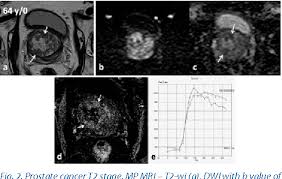

Like other types of cancer, prostate cancer is class. It may grow slowly and it's typically treatable. Prostate cancer staging is based on biopsy results including the gleason score, psa levels and other exams. Prostate cancer staging is vital because it is used to guide the treatment plan and predict the patient's prognosis. Please understand that our pho. We'll talk about what that means. Find information on the four stages of prostate cancer. One in seven men in the united states will receive a prostate cancer diagnosis during his lifetime. A diagnosis of lung cancer naturally causes some overwhelming emotions, but you don't have to let those emotions get the best of you. Stage 3 prostate cancer is an advanced but still treatable form of the disease. However, as with other types of cancer,. But hearing the words can still be scary. Stage 3 prostate cancer is more advanced, but it is still very treatable.

One in seven men in the united states will receive a prostate cancer diagnosis during his lifetime. Information is a powerful weapon against uncertainty and fear, and you can use this to your advantage. Prostate cancer is a common type of cancer in men, according to the mayo clinic. Prostate cancer staging is based on biopsy results including the gleason score, psa levels and other exams. Stage 3 prostate cancer is an advanced but still treatable form of the disease. Learn more about prostate stages here. The earlier the detection of prostate cancer, the better the patient's chance of survival is. We'll talk about what that means.